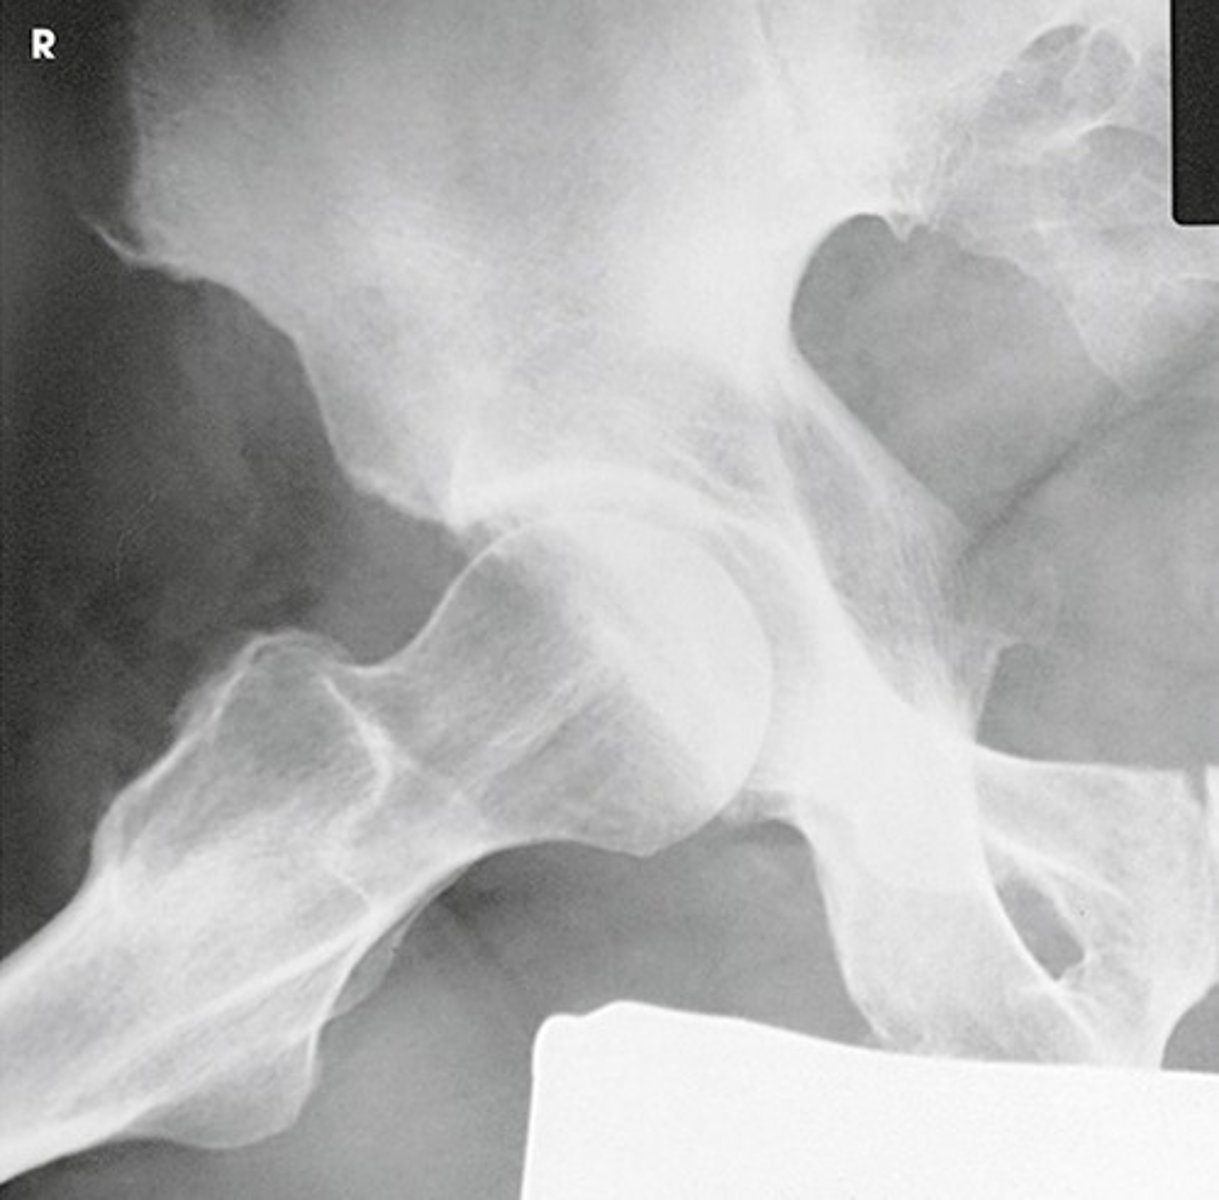

Identify the projection:

AP Hip

Axiolateral Hip (Danelius-Miller)

AP oblique hip (Modified Cleaves)

Lateral hip (Lauenstein)

AP oblique hip

Lateral hip

Axiolateral hip